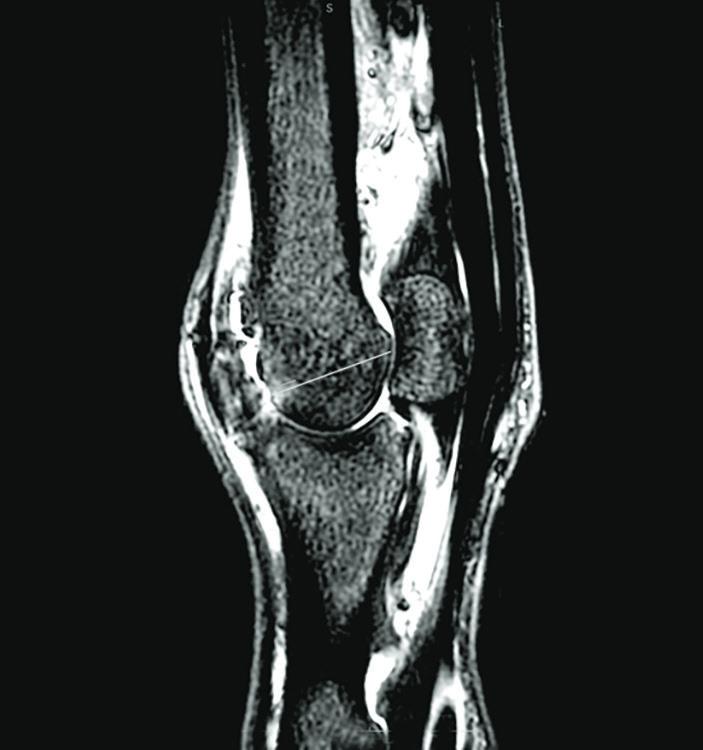

Fetlock MRI of a Horse with Osteoarthritis

In the second study, 10 million stem cells per vial were frozen for use in healing osteoarthritis from fetlock chips in horses that were previously conditioned to be fit. After the fetlock chip was created, exercise commenced for six more weeks and then osteoarthritis was evaluated by MRI for a baseline. Half the horses were treated with the pooled MSCs and the control group received saline before another month of exercise. Then MRI and lameness exams were repeated, as well as arthroscopy to score the cartilage and remove the chip.

MRI revealed that the horses treated with stems cells had less progression of osteoarthritis. “They were less lame when exercised after the stem cell therapy than the horses that received saline,” says Koenig.